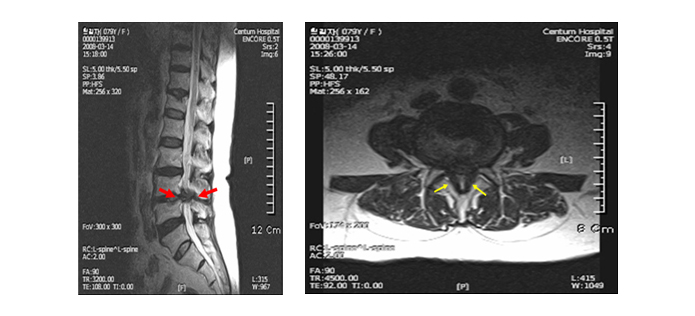

척추관 협착증이란 척추 중앙의 척추관, 신경근관 또는 추간공이 좁아져서 허리의 통증을 유발하거나 다리에 여러 복합적인 신경 증세를 일으키는 질환을 뜻합니다.

척추관이란 척추 가운데 관 모양의 속이 빈 곳으로 아래 위 척추에 의해 추간공이 생기며 가운데 관 속은 뇌로부터 팔다리까지 신경(척수)이 지나가는 통로가 됩니다.

척추관 협착증은 요추부에 주로 많이 발생을 하게 되어 척추강 협착증(요추관 협착증)이 좀 더 정확한 표현입니다.